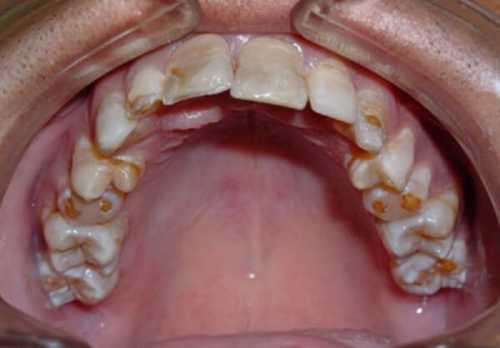

Черноватая окантовка на шейке зуба может быть при употреблении растворимых препаратов железа или хроническом воспалите льном процессе осаждение бактерий группы лептотрихий. Желтовато коричневое окрашивание зубов чаще связано с употреблением антибиотиков матерью во второй половине беременности или ребенком в период формирования зубов. Желтовато зеленоватое окрашивание развивается при тяжелых нарушениях обмена билирубина и гемолитических разрушение эритроцитов состояниях. Красноватое окрашивание эмали зубов характерно для врожденного нарушения обмена пигмента порфирина. Это заболевание называется порфирией. Аномалии прикуса возникают изза неравномерного роста челюстей, изза длительного сосания сосок. Аномалии расположения зубов возникают по конституциональным причинам малые размеры челюсти, изза травм, при врожденном нарушении обмена соединительной ткани, при опухолях альвеолярного отростка челюсти. Отсутствие зубов до года крайне редко связано с адентией отсутствием их зачатков. Проверить наличие зубных зачатков можно с помощью специального метода радиовизиографии по назначению детского стоматолога.